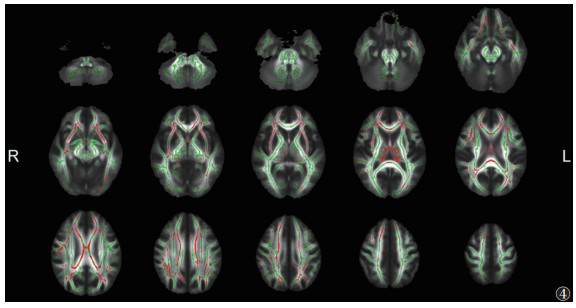

与HC组相比,ITB组脑白质的FA广泛降低、MD升高更广泛(P<0.05,TFCE和FWE校正)(图 2,3)。其中胼胝体体部、胼胝体压部、双侧前放射冠等的FA和MD同时改变(图 4)。

| 注:与HC组相比,ITB组脑白质FA降低和MD升高的重叠区域显示为红色(P<0.05,TFCE和FWE校正)。脑白质骨架显示为绿色。L,左;R,右 图 4 ITB组与HC组FA、MD的差异重叠区域 |